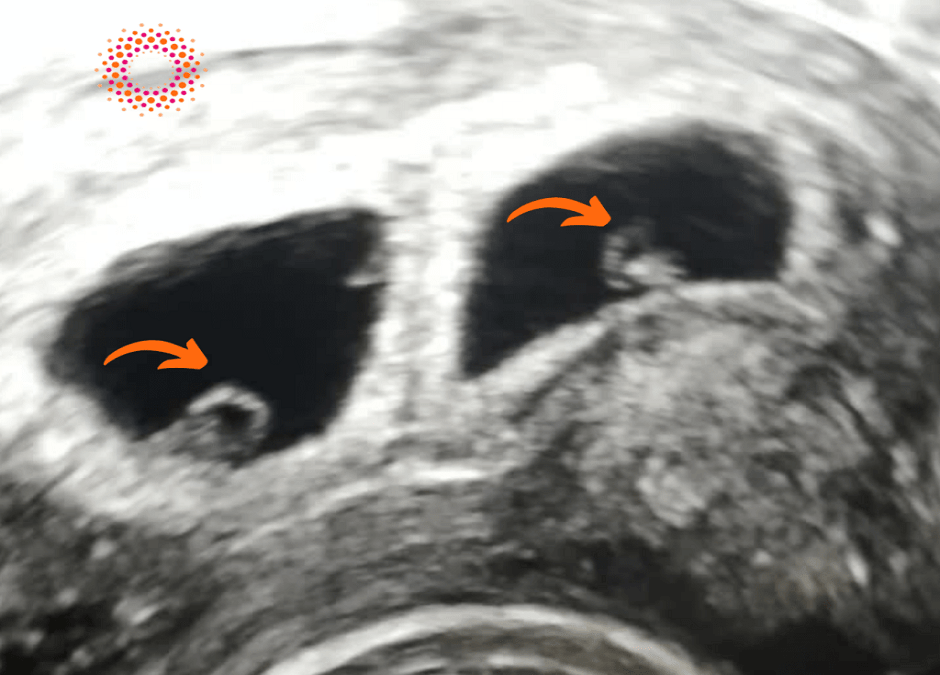

Ας εξηγήσουμε λίγο καλύτερα τι βλέπουμε στη φωτογραφία: απεικονίζεται η μήτρα και 2 σάκοι κύησης. Το πορτοκαλί βελάκι μας δείχνει τη θέση των εμβρύων μέσα στο σάκο.

Στον 1ο υπέρηχο θέλουμε να δούμε τον αριθμό των σάκων και να επιβεβαιώσουμε ότι έχει γίνει εμφύτευση εντός της ενδομητρικής κοιλότητας, ανεξάρτητα αν έχει γίνει εξωσωματική ή αν πρόκειται για φυσιολογική σύλληψη. Διαδοχικά βλέπουμε τον λεκιθικό ασκό, το εμβρυικό στοιχείο και την καρδούλα.